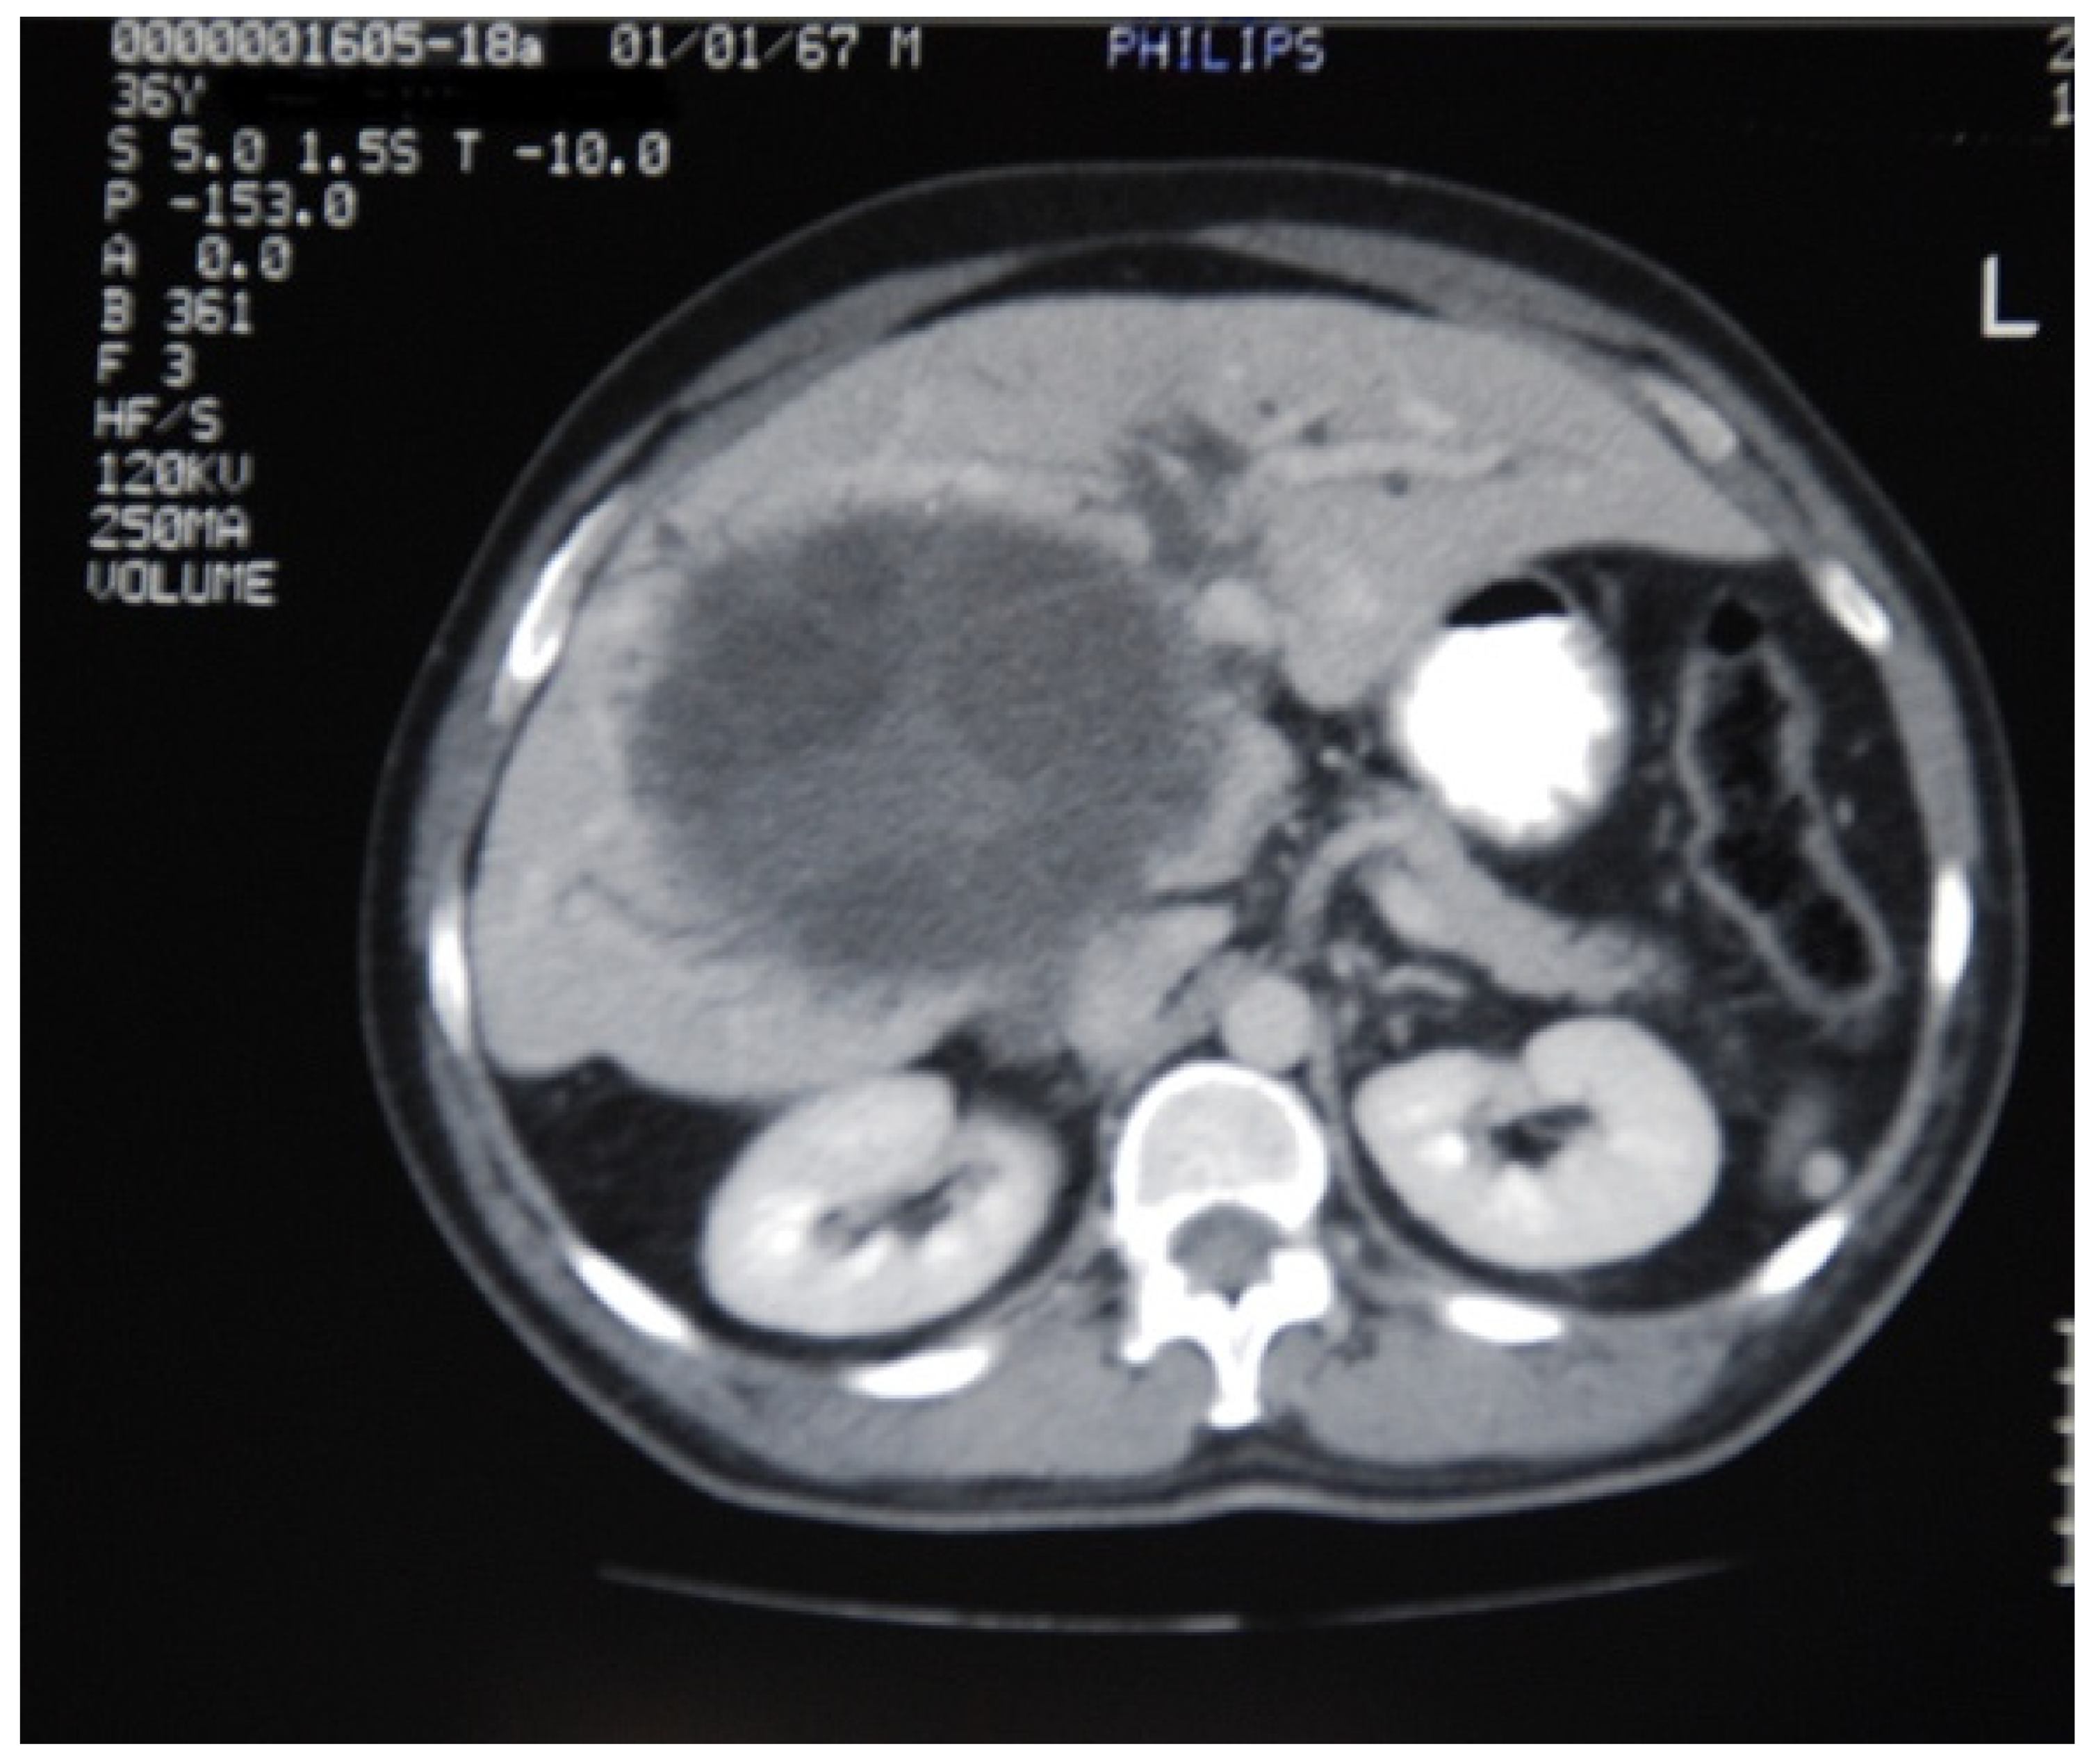

| Computer Tomography | 2/6 (33%) | 1/6 (17%) | 2/2 (100%) | 2/2 (100%) | 1/2 (50%) | 8/18 (44%) |